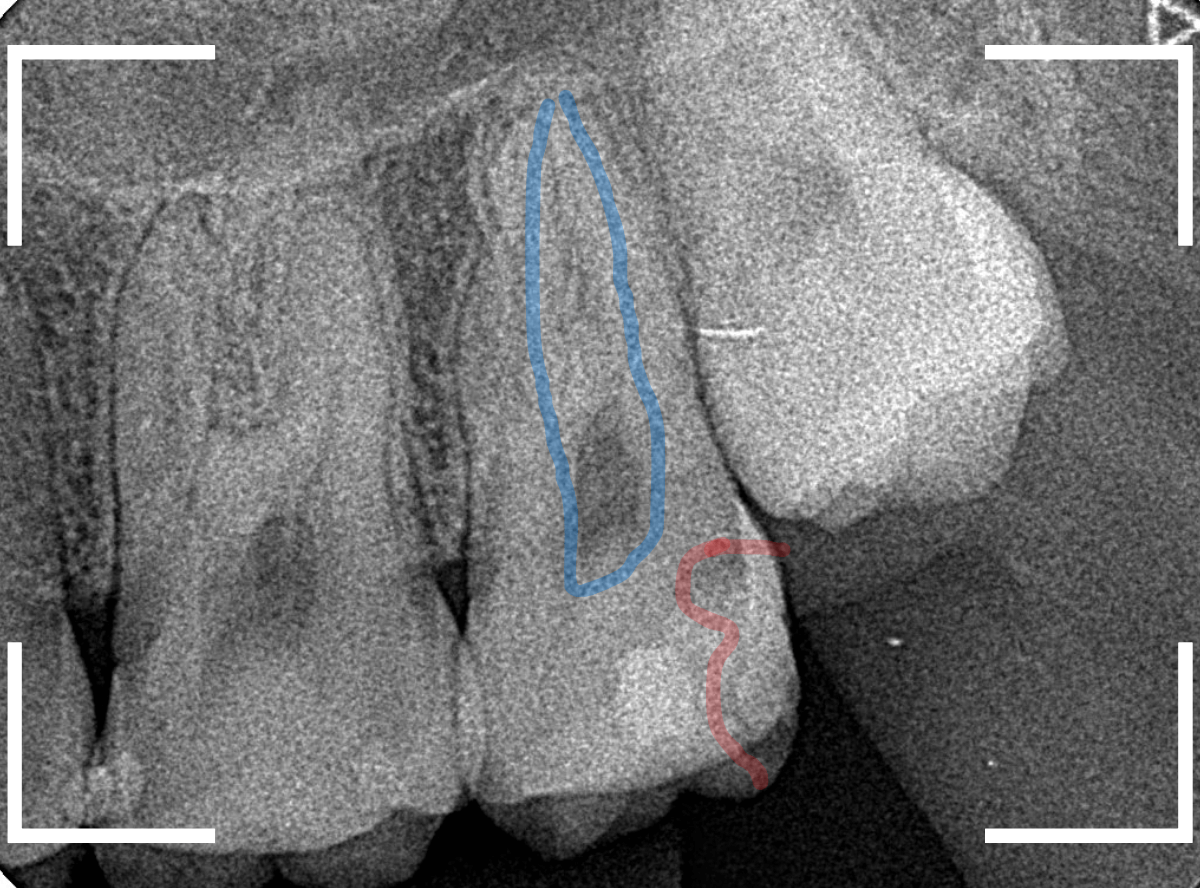

レントゲン写真です。

レントゲン写真で確認します。

青い線が歯の神経、赤い線が虫歯です。

おやしらずがあった際にはわかりづらかったですが、歯の後ろ側のおやしらずが重なっていたところが虫歯になっているのがわかります。

おやしらずが原因で、このように手前の歯が虫歯になってしまう事が多いために、抜歯を勧められる事が多いのです。

そして、虫歯の部分におやしらずが被さっていたために、しみる症状などを感じなかったのです。